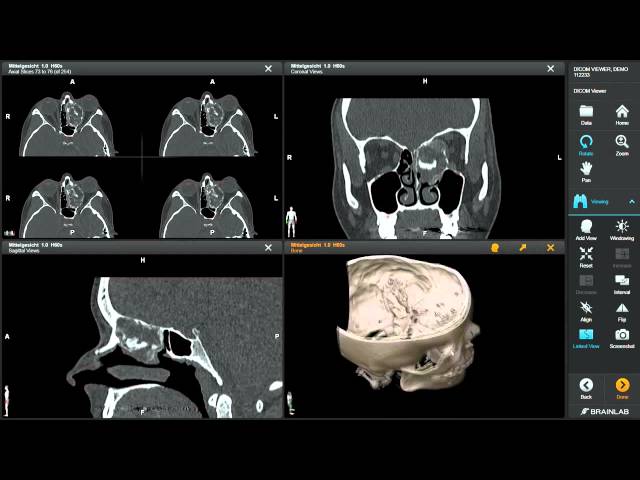

DICOM viewers have more than simple image display functions. They understand embedded metadata and visual data. This is because window leveling assists in contrast optimization to diagnose properly. There is zoom and pan functionality.

Multi-series and multi-frame navigation facilitates complicated research. Anatomical measurements are evaluated with the help of measurement tools. Clinical reporting is facilitated by the use of annotation features. There is the support of modality; it consists of CT, MRI, ultrasound, and X-ray.

The concept of remote access has gained more relevance in the medical field. Web-based viewers can also be used via off-site consultation with secure web-based viewers. Distributed care teams are supported by cloud-enabled systems.

Sharing and teamwork on cases. Multidisciplinary collaboration on shared cases is possible on medical image viewer platforms. Access to real-time information minimizes the delay of diagnostic complaints. Storing centrally helps maintain the consistency of the availability of images.

Peer review and second opinion tools are supported by collaboration tools. Flexibility is improved through mobile compatibility. Trusted remote viewing will guarantee continuity of care. Positive teamwork enhances the diagnostic performance and patient outcomes.